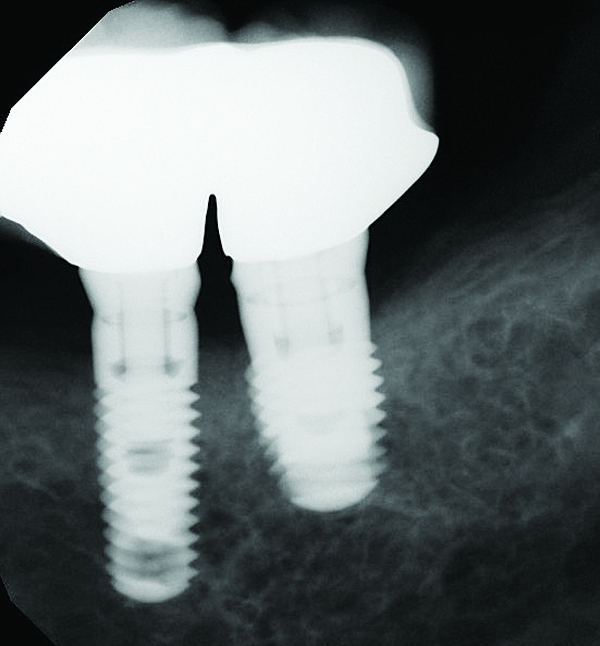

Fig 7 through Fig 14. Periapical radiographs of a 62-year-old woman who received a fixed porcelain-fused-to-metal reconstruction supported by abutments by internally connected dental implants. Fig 7 through Fig 10 are at initial prosthesis placement: mandibular site Nos. 30 and 29 (Fig 7); mandibular site Nos. 26, 25, and 23 (Fig 8); mandibular site Nos. 23 and 21 (Fig 9); mandibular site Nos. 21 through 19 (Fig 10). Fig 11 through Fig 14 are 11 years later (2013) and show excellent preservation of the vertical bone levels around the implants: mandibular site Nos. 30 and 29 (Fig 11); mandibular site Nos. 26 and 25 (Fig 12); mandibular site Nos. 25 and 23 (Fig 13); mandibular site Nos. 20 and 19 (Fig 14). It is interesting to note that in the mandibular right posterior quadrant there is a matched pair, ie, an external hex dental implant (No. 30) adjacent to an internally connected dental implant (No. 29). The bone levels around each of these designs are well-preserved at the 11-year follow-up.